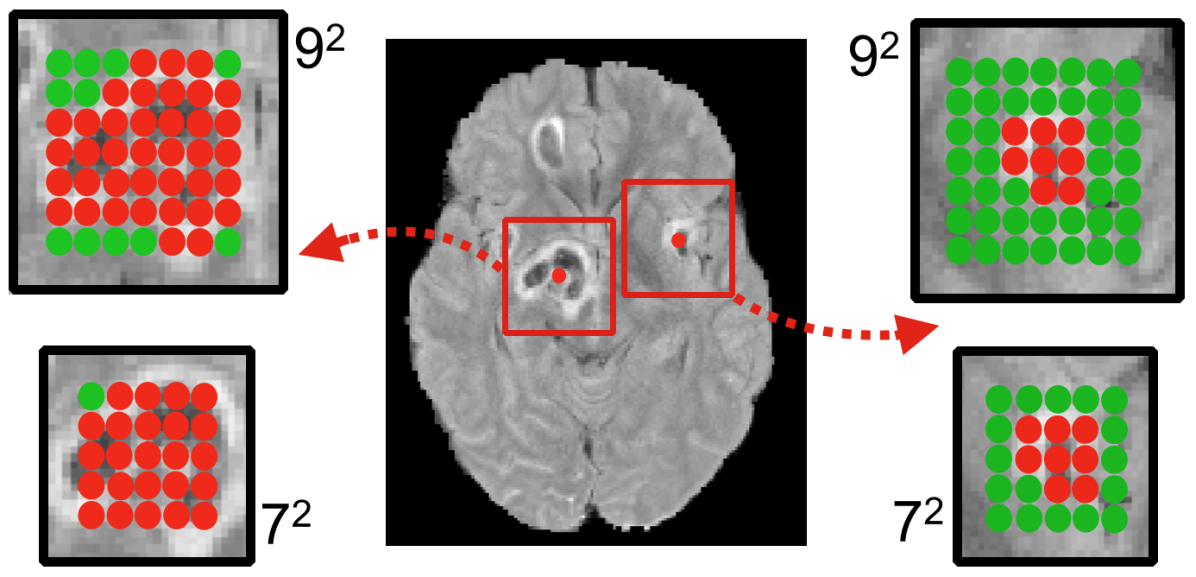

An appealing consequence of this scheme is that the sampling of input segments provides a flexible and automatic way to balance the distribution of training samples from different segmentation classes which is an important issue that directly impacts the segmentation accuracy. Specifically, we build the training batches by extracting segments from the training images with 50% probability being centred on a foreground or background voxel, alleviating class-imbalance. Note that the predicted voxels in a segment do not have to be of the same class, something that occurs when a segment is sampled from a region near class boundaries (Fig. 3). Hence, the sampling rate of the proposed hybrid method adjusts to the true distribution of the segmentation task’s classes. Specifically, the smaller a labelled object, the more background voxels will be captured within segments centred on the foreground voxel. Implicitly, this yields a balance between sensitivity and specificity in the case of binary segmentation tasks. In multi-class problems, the rate at which different classes are captured within a segment centred on foreground reflects the real relative distribution of the foreground classes, while adjusting their frequency relatively to the background.